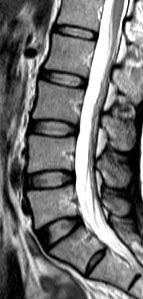

今次的研究是一項以南中國地區人口而作出的具代表性抽樣研究,從上述大型人口群組中抽出21歲或以上的成年人為研究對象。在是次的研究中,研究人員分析了合共2,599位成年人的磁力共振(MRI)檢查數據。當中27%(709人)沒有椎間盤退化,而73%(1,809人)則有椎間盤退化。在患有椎間盤退化的成年人當中,有7%體重過輕,48%體重正常,36%過重和9%肥胖。超重及肥胖的成年人出現椎間盤退化程度及發展成更嚴重的病徵的機會,比正常體重或過輕的成年人嚴重。